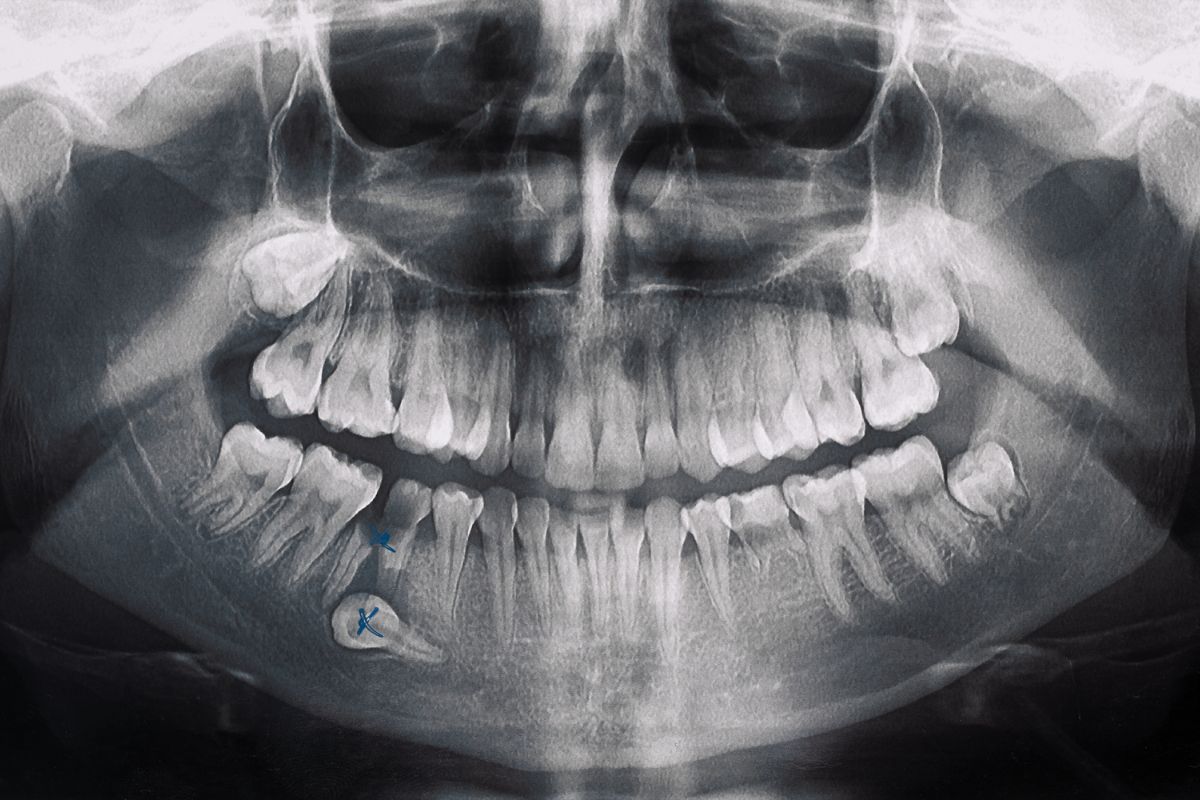

Most people think of bright, perfect smiles when they hear the term cosmetic dentistry. While cosmetic dentists help improve aesthetics, they can also provide restorative services like cavity treatment. At Knoxville Smiles at Malone & Costa Dentistry, we marry form and function to create healthy, beautiful smiles. Cosmetic Dentistry and Cavity Care in Knoxville What Are Cosmetic Fillings? Cosmetic fillings, or composite fillings, address cavities by maintaining the natural look of the teeth. The process involves removing the decayed portion of the tooth, cleaning the affected area, and then filling it with the tooth-colored resin. Unlike traditional metallic fillings, cosmetic … Continue reading